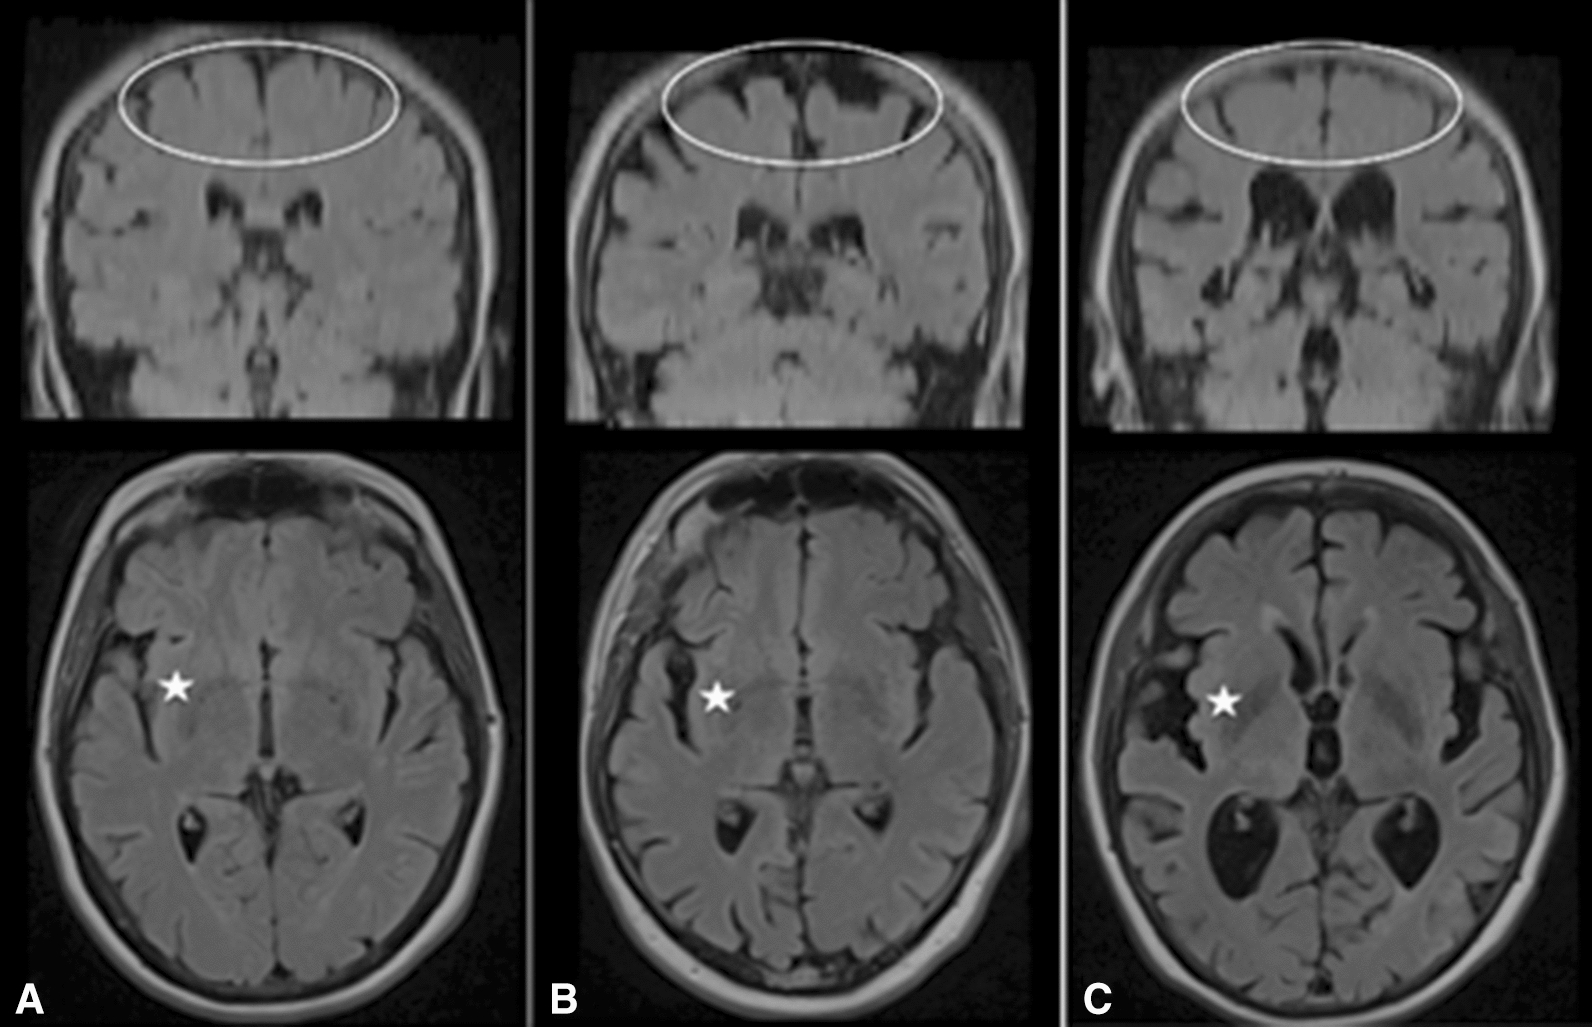

Fig. 2.

Examples of “normal,” unspecific “atrophy,” and “iNPH” subjects. T2-weighted Fluid inversion recovery (FLAIR) coronal (upper row) and axial (lower row) images of A “normal,” B unspecific “atrophy” (note atrophy of both the apex, Sylvian fissures, and mild enlargement of the lateral ventricles) and C “iNPH” (note the discrepancy between the relatively tight apex, wide Sylvian fissures and ventricles). Ellipse shows apex. One of the Sylvian fissures is located left of the star